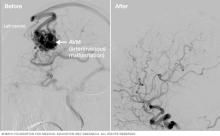

Brain arteriovenous malformation treatment results

Brain AVM before and after Gamma Knife treatment

Brain arteriovenous malformation (AVM) before Gamma Knife treatment (left) and 52 months after the procedure (right)